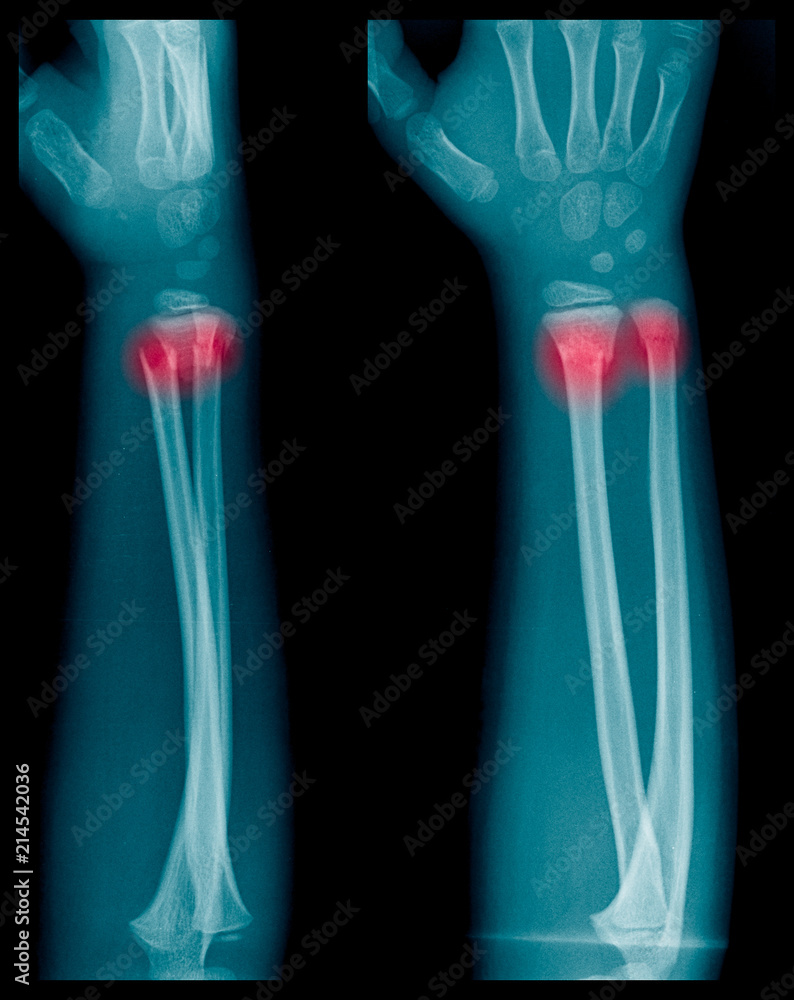

Xray image of Forearm bone fracture in child's (Radius bone, Ulna bone) Technology Stock Photos Radius And Ulna Fracture In Child both bone forearm fractures are one of the most common pediatric fractures, estimated around 40% of all. The ulna bone is on the pinky. It is made up of two bones: Forearm fractures are common in childhood,. The radius and the ulna. The forearm is made up of two bones, the ulna and the radius. A forearm fracture can. Radius And Ulna Fracture In Child.

Xray image of Forearm bone fracture in child's (Radius bone, Ulna bone) Stock Photo Adobe Stock Radius And Ulna Fracture In Child The forearm is made up of two bones, the ulna and the radius. the initial management of distal forearm fractures in children will be reviewed here. Forearm fractures are common in childhood,. The ulna bone is on the pinky. radius and ulna are attached by the proximal annular ligament, by the interosseous membrane along the. ulna and. Radius And Ulna Fracture In Child.